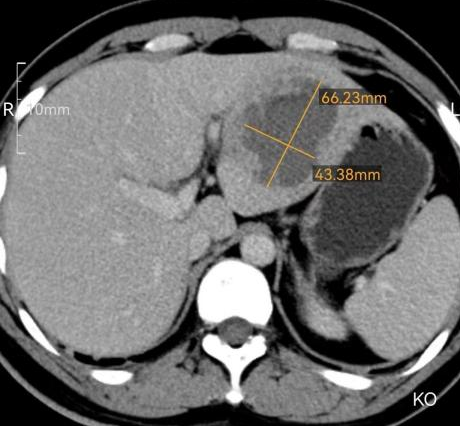

术前增强CT结果:肝脏占位,考虑脓肿。面积约6.7cm*4.4cm